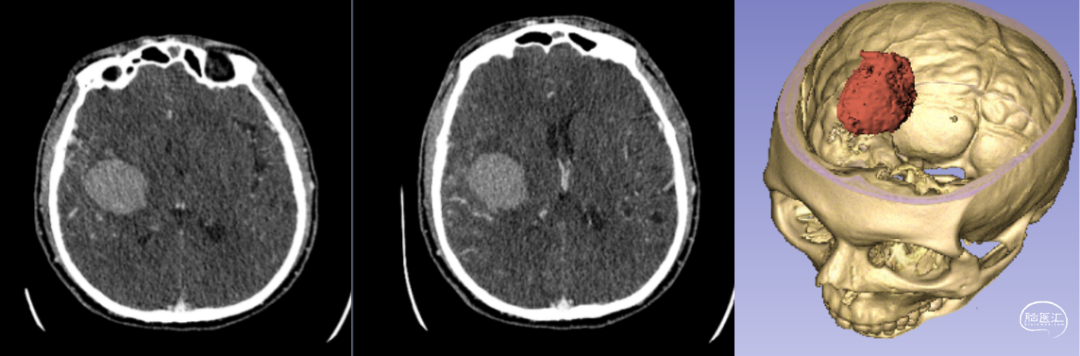

新疆醫科大學第一附屬醫院神經外科中心已成功將該技術應用于多例腦卒中患者的治療。以一例典型病例為例:[14]

- 患者情況:52歲女性,因“右側肢體無力1天”就診,入院時呈淺昏迷狀態,雙側瞳孔等大等圓(直徑約3.5mm),對光反射遲鈍,右側肢體肌力為0級。

- 手術過程:基于術前影像數據,團隊利用3D打印技術設計并制作個性化手術導板,精準定位血腫位置后實施穿刺引流。術后復查頭部CT顯示,引流管準確位于血腫腔內,血腫清除效果良好。